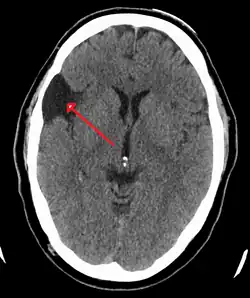

Arachnoid cyst

Arachnoid cysts are cerebrospinal fluid covered by arachnoidal cells and collagen[1] that may develop between the surface of the brain and the cranial base or on the arachnoid membrane, one of the three meningeal layers that cover the brain and the spinal cord.[2] Primary arachnoid cysts are a congenital disorder whereas secondary arachnoid cysts are the result of head injury or trauma.[3] Most cases of primary cysts begin during infancy; however, onset may be delayed until adolescence.[2]

Diagnosis

Diagnosis is principally by MRI. Frequently, arachnoid cysts are incidental findings on MRI scans performed for other clinical reasons. In practice, diagnosis of symptomatic arachnoid cysts requires symptoms to be present, and many with the disorder never develop symptoms.